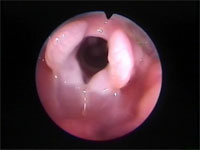

Abb 6 Laryngeales-Ödem

Abbildung 6: Larynx nur noch halb geöffnet. Die Stimmbänder liegen bereits eng aneinander.

Abb 7 Rima-offen-Plica-zu

Abbidlung 7: Weiter fortschreitender Laryngospasmus gegenüber Abbildung 6.

Abb 8 Schlüsselloch-beim-Laryngos

Abbildung 8: Laryngospasmus - nur noch das kleine obere „Schlüsselloch“ der Rima glottidis ist geöffnet.

Selbst bei ausgeprägtem Laryngospasmus bleibt bei der Katze im dorsalen Bereich der Rima glottidis eine winzig kleine Öffnung erhalten. Dieses „Schlüsselloch" kann man bei der Notintubation der Katze (siehe unten) immer mit einem dünnen Mandrin passieren, selbst wenn die Stimmlippen fest aneinander gepresst sind. Für eine funktionelle Atmung reicht die kleine Öffnung jedoch keinesfalls aus.

Der Laryngospasmus führt häufig zu einer vollständigen Blockade des Atemweges und Asphyxie.

Abbildung 9: Laryngospasmus – Rima glottidis vollständig verschlossen. Auch das „Schlüsselloch“ ist nicht mehr sichtbar. Dennoch kann an dieser Stelle der Mandrin behutsam eingeführt werden.